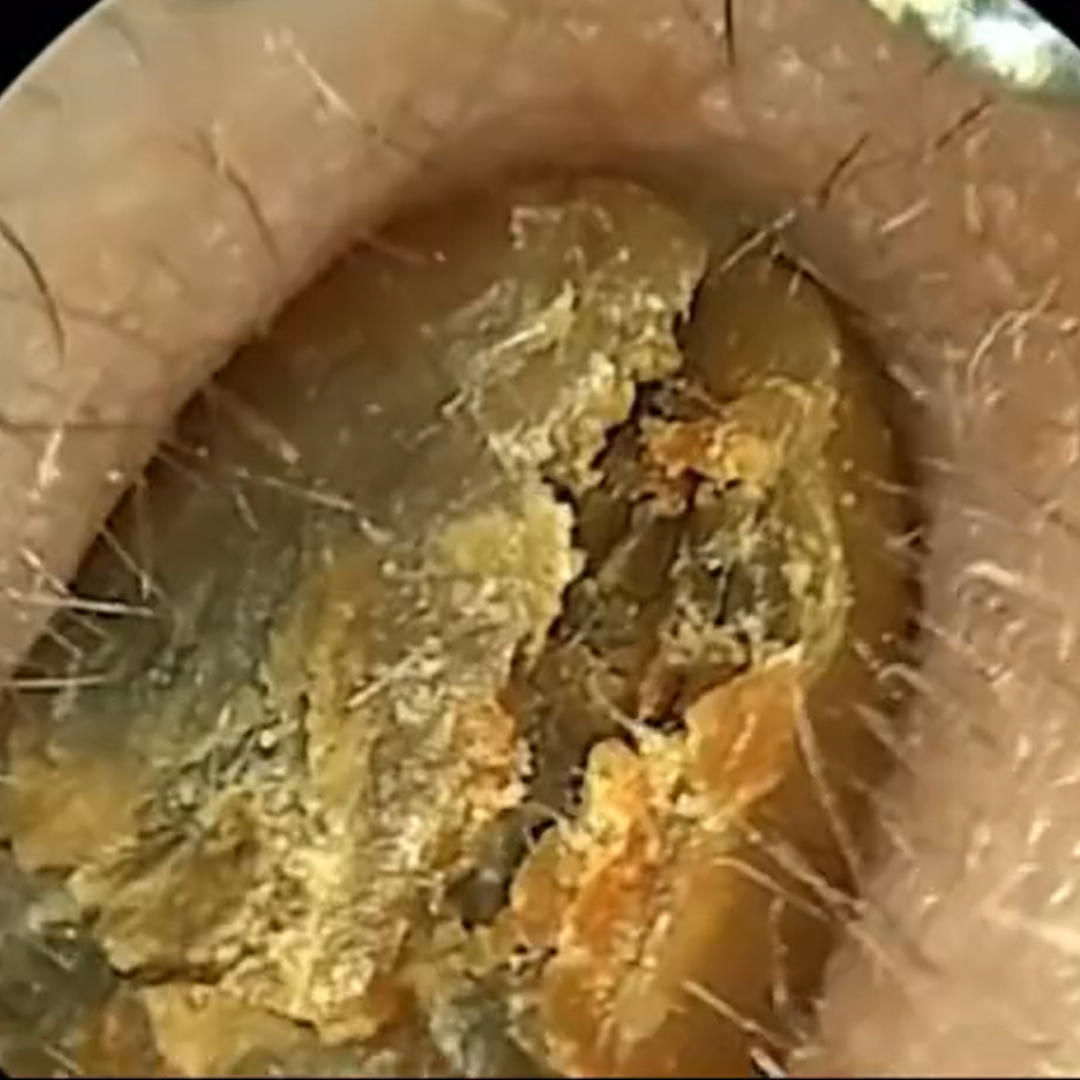

✅ Wyraźny obraz HD – dokładna widoczność wnętrza ucha dzięki kamerze 1080p

Koniec z ryzykiem urazów i infekcji — patyczki często powodują podrażnienia, infekcje i perforację błony bębenkowej. Pełna kontrola dzięki obrazowi HD 1080p — widzisz woskowinę i swobodnie ją usuwasz, zamiast ją wpychać.

Pełna kontrola dzięki obrazowi HD 1080p — widzisz woskowinę i swobodnie ją usuwasz, zamiast ją wpychać. Miękkie silikonowe końcówki zamiast patyczków — precyzyjnie usuwa woskowinę, bez ryzyka zarysowań i dyskomfortu